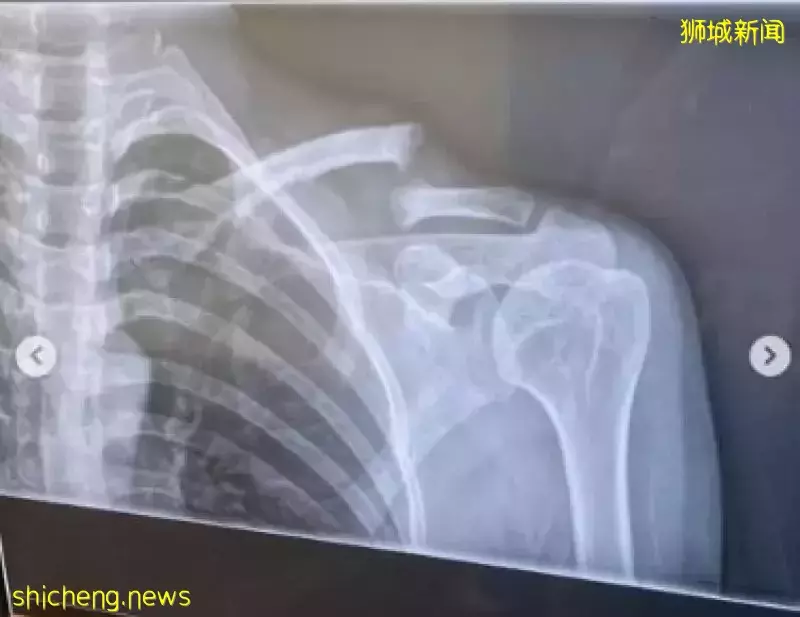

赵彩聆前晚(3月25日)在IG晒出两张照片,一是坐着轮椅,另一是X光照片,透露她骑脚踏车发生意外,伤及锁骨,需要动手术。

赵彩聆说,意外发生后,她被送往医院检查,医生证实她的锁骨骨折,下星期需要进行骨骼组织移植(bone graft)手术。也因为如此,她被迫取消手头上的工作。

赵彩聆锁骨骨折需动手术。(图:艺人IG)